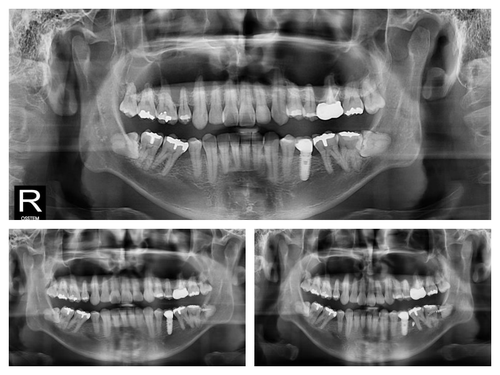

사랑니가 옆으로 누워있고 신경이라 가까워서 큰 병원 가서 뽑으래요~

사랑니 발치시 신경손상 위험성으로 치과 교정용 스크류를 이용하여 교정치료와 함께 안전하게 사랑니를 발치한 케이스입니다.

교정력으로 사랑니 뿌리가 신경관과 멀어지기 시작